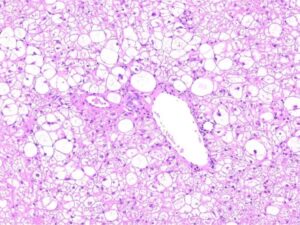

ワンちゃんが乳腺にできた複数のシコリを気にされて来院されました。bilateral mastectomyで対応しました。摘出後の病理組織検査の結果は、「R3-4間腫瘤:乳腺癌(複合型)」でそれ以外は「良性乳腺混合腫瘍」でした。無事元気に退院し、その後再発もなく経過は良好です。よかったね。